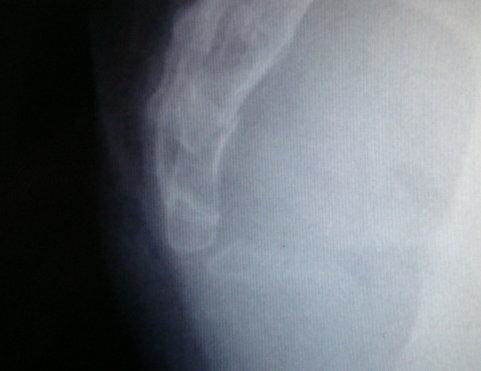

一抬臀部尾骨疼